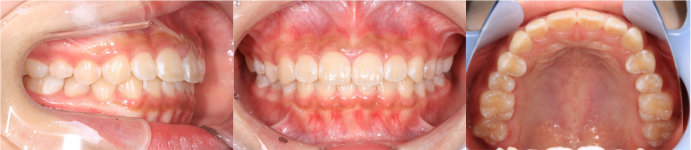

| Case11 |

| 受け口 および 右上の乳臼歯が早期に抜けたことにより、その後ろにある6歳臼歯が前方にずれている。そのため、6歳臼歯の直前にある永久歯が生える隙間がない。 |

| <治療前> |

|

| <治療後> |

| 主訴 |

前歯が反対になっている |

| 診断名 |

上顎右側第二乳臼歯の早期喪失による上顎右側第一大臼歯の近心転位、それに伴う上顎右側第二小臼歯の萌出スペース不足を伴う反対咬合

| 年齢 |

10歳 |

| 使用装置 |

マルチブラケット装置 |

| 抜歯部位 |

永久歯の抜歯は無し |

| 治療期間 |

3年8か月 |

| 治療費概算 |

検査・診断料:5万円+税 装置・技術料:25万円+税 来院ごとの処置・管理料:5,000円+税 保定装置料:5万円+税 |

| リスク・副作用 |

特になし |